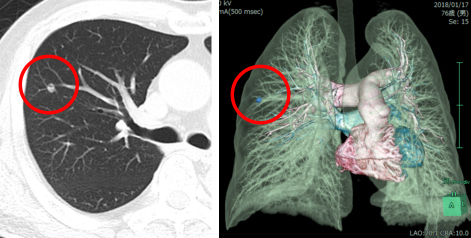

56歳女性。横行結腸癌同時性肝転移(肝S8)+傍大動脈リンパ節転移を認め当センターへ紹介となりました。B-mab+XELOX 3コース施行で著効を示し、PETでもnear CR(図1)となりました。腹腔鏡下肝部分切除術+右半結腸切除術を施行しました(図2−4)。手術時間は8時間25分、出血量は50g。術後14日目で退院となりました。原発巣、肝転移巣ともに病理学的CRでした。

図1 化学療法前後の画像評価:下部消化管内視鏡・造影CT・PET、それぞれの画像

CT-colonographyとSMA、SMV、3D構築の画像

図2 術前シミュレーション